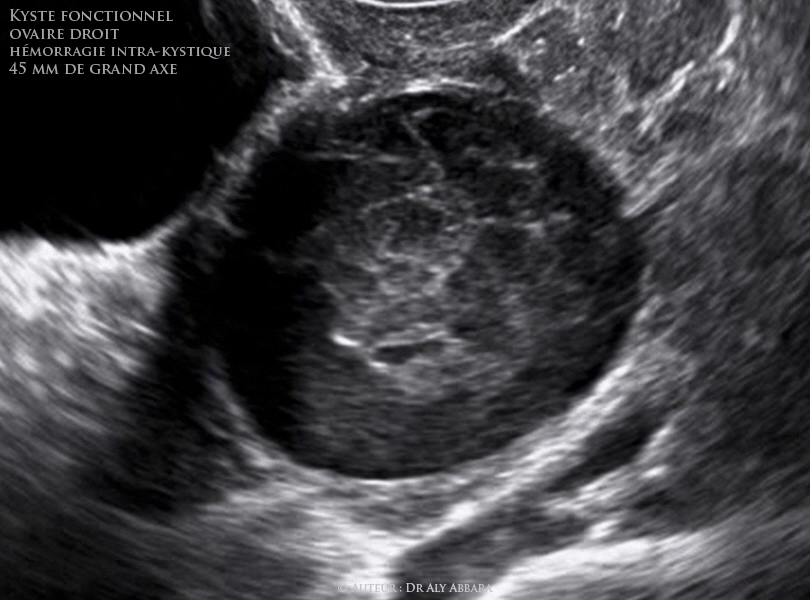

Kyste Ovarien Fonctionnel Hemorragie Intrakystique Prenant L Aspect Echographique D Un Endometriome

Kyste Ovarien Fonctionnel Hemorragie Intrakystique Prenant L Aspect Echographique D Une Composante Solide Evoluant Dans La

Kystes Ovariens Fonctionnels Les Differents Aspects Echographiques De L Hemorragie Intra Kystiques